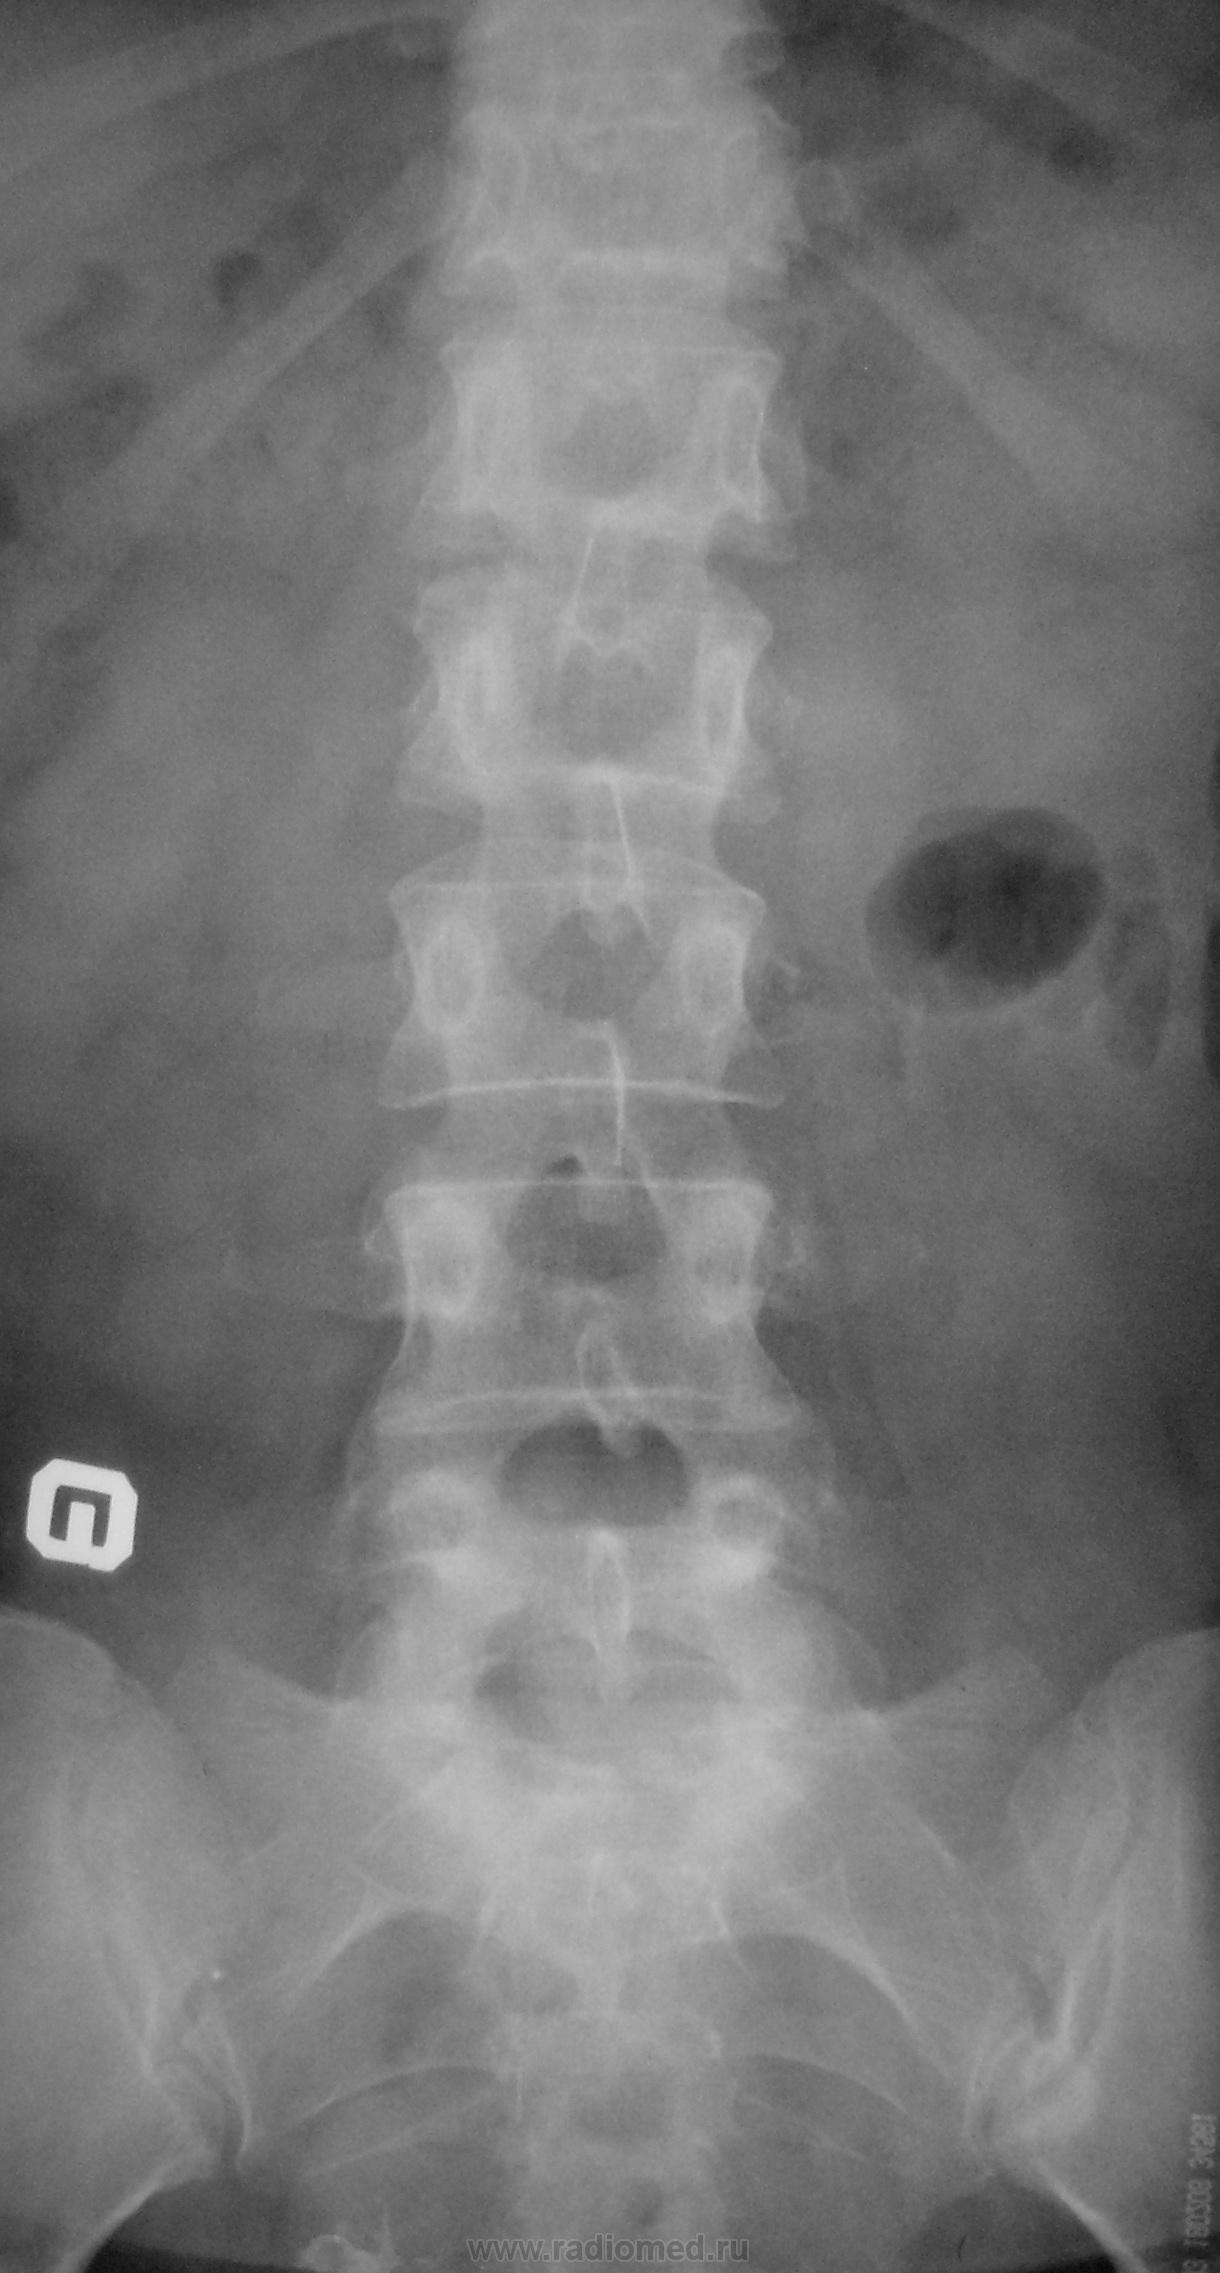

Пол пациента: Женский пол Тип патологии: Врожденная патология Область исследования: Скелетно-мышечная система Методы исследования: Rg Молодая женщина пришла на снимок поясничного отдела. Другая женщина, которая занимается рукопашным боем, обратилась с жалобами на боли в пояснице, после неудачного броска. https://radiomed.ru/sites/default/files/styles/case_slider_image/public/user/712/sl274202.jpg?itok=nrVgJub5 https://radiomed.ru/sites/default/files/styles/case_slider_image/public/user/712/sl274211.jpg?itok=ON6uvgKI https://radiomed.ru/sites/default/files/styles/case_slider_image/public/user/712/sl274212.jpg?itok=NmuMvaE1 https://radiomed.ru/sites/default/files/styles/case_slider_image/public/user/712/sl274213.jpg?itok=nP2dg6tE ID:18475 Пт, 27/01/2012 - 18:10 #1 Фаина Не на сайте Был на сайте: 2 года 11 месяцев назад Зарегистрирован: 14.12.2008 - 16:51 Публикации: 323 В первом случае, кроме остеохондроза и несросшихся апофизов, честно говоря, ничего критичного" не увидела. А во втором случае, не спондилолиз ли в L5?! Пт, 27/01/2012 - 18:17 #2 Наталия Не на сайте Был на сайте: 8 лет 7 месяцев назад Зарегистрирован: 30.07.2008 - 13:24 Публикации: 538 Во втором случае вероятнее спондилолиз. Пт, 27/01/2012 - 18:25 #3 Глазков Игорь А... Не на сайте Был на сайте: 9 месяцев 1 неделя назад Зарегистрирован: 19.12.2008 - 20:41 Публикации: 1597 Шморля в каудальной части тела позвонкаТ12 Прийди к Себе Пт, 27/01/2012 - 21:15 #4 И.Бондаренко Не на сайте Был на сайте: 3 дня 7 часов назад Зарегистрирован: 13.09.2011 - 22:55 Публикации: 9206 Случай №1. Грыжа Шморля Т12, несросшиеся апофизы L2,5 или обызвествившиеся грыжи дисков. Случай №2. Спондилолиз дужки L5. Ср, 01/02/2012 - 21:08 #5 Natalja Не на сайте Был на сайте: 13 лет 10 месяцев назад Зарегистрирован: 27.01.2012 - 22:08 Публикации: 4 Глазков Игорь Артурович wrote: Молодая женщина пришла на снимок поясничного отдела. Другая женщина, которая занимается рукопашным боем, обратилась с жалобами на боли в пояснице, после неудачного броска. В первом случае смущает L2, травмы не было? Чт, 02/02/2012 - 14:35 #6 Глазков Игорь А... Не на сайте Был на сайте: 9 месяцев 1 неделя назад Зарегистрирован: 19.12.2008 - 20:41 Публикации: 1597 травму отрицает Прийди к Себе

Во втором случае вероятнее спондилолиз.

Случай №2. Спондилолиз дужки L5.